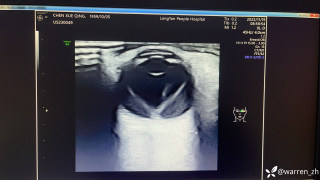

整个右侧胸腔被滚烫的铝水烧穿,多根肋骨骨折、碳化、坏死,背腹部和面部也有大面积烧伤……右肺完全暴露在外,被压缩到只剩一半的体积。这样的病人,还救得活吗?300℃ 铝水烧了 10 分钟,整个右胸都烧穿了时间拨回到 2024 年 9 月 26 日,下午 15 点,救护车的警笛声撕破了浙江大学医学院附属第二医院(文内简称「浙大二院」)解放路院区的平静。警笛声由远及近,停在了急诊的门口。不多时,一群人冲进急诊。「300 多度的铝水烧了 10 分钟,整个右胸都烧穿了!」负责转运的同事几乎是咆哮着喊出这句话。急诊医学科的许永安主任医师看到患者情形时,心下一惊。本该完整的右侧胸腔,现在成了一个焦黑的大洞,大